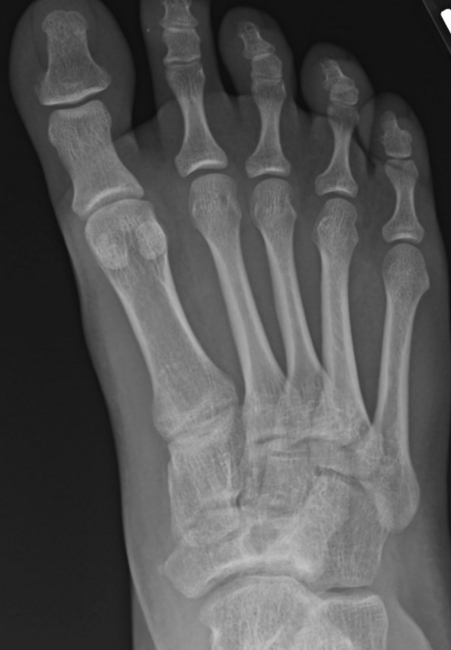

As the Ponseti grew in popularity, I noted significant discrediting of surgical options. Well long-term studies on the Ponsetti are starting to surface, and it is not without its own problems. Kids are lost to follow-up, not braced appropriately, and just like we saw in long-term studies with the posteromedial release, there is a lot of undercorrection. Casting cannot and will not ever achieve what the Cincinnati release can. Although the Ponseti may not have the complications of the Cincinnati, X-ray data reveals that the Ponseti cannot and does not correct everything, most critically, talocalcaneal angles. You can not solve a clubfoot with an Achilles tenotomy and an overly aggressive casting. As these kids develop, I see residual met adductus and calcaneal varus, along with casting complications like flat top talus and met primus elevatus. I then see that they will develop DJD just like posteriomedial and Cincinnati releases. Haasbeck and team in 1997 reported that the Cincinnatti required fewer procedures than the posteromedial release over the life of their study.14 Thomas performed a systematic review in 2019, concluding that the longer the study follow-up, the greater the relapse rate and the poorer the results of the Ponseti.15 For most of us who have done clubfeet surgery for many years, this is no surprise. Among the 46 studies meeting inclusion criteria, they saw as high as 67 percent required future surgeries to address relapse.15

As a quick history lesson, in my experience, clubfoot casting was the norm up until the 1980s. Posteromedial releases dwindled in popularity in the early 1990s, when Cincinnati releases just became popular, during my training time. By the 2000s, providers championed the Ponseti technique. As I started to see more and more soldiers with clubfeet trying to join the military, I saw more cases that needed medical discharge or revision surgeries. Posteromedial release historically had residual met adductus and calcaneal varus or often already presented with early DJD.

Here is a typical case presentation. A 21-year-old Marine at Ft. Leonard Wood for training underwent a Cincinnati release at one year old and had stellar follow-up. Her surgeon even wrote her medical waiver for entrance into the Marines. She ran track in high school. She finished boot camp and completed all of her Marine training, but now has chronic pain. She no longer can run. She hasn’t passed her physical training in over a year. She developed talonavicular DJD. By all accounts, her overall clubfoot should be rated an A+; no residual deformity, normal talocalcaneal angles on AP and lateral views, no equinus, no residual varus, only slight met primus elevatus, but no signs of a flattop talus. Clinically, she lacks subtalar range of motion, which I commonly find post-clubfoot release of any kind. So many in the military do very well for a while, but the demands of the military eventually catch up to them. We all root for clubfeet to make it, but the odds are stacked against them.